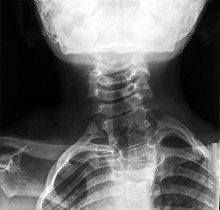

Question 3:

A 25-year-old male is involved in a high-speed motor vehicle collision. Radiographs demonstrate a traumatic spondylolisthesis of the axis (Hangman's fracture) with an oblique fracture line through the pars interarticularis, minimal translation, but extreme angulation (>11 degrees). The C2-C3 disc space appears disrupted posteriorly. According to the Levine-Edwards classification, what is the most appropriate initial management for this specific injury pattern (Type IIa)?

Correct Answer: Halo vest applied with gentle compression and extension

Explanation:

The scenario describes a Levine-Edwards Type IIa Hangman's fracture. This injury is caused by a flexion-distraction mechanism, leading to severe angulation with minimal initial translation. A critical point in management is that axial traction is STRICTLY CONTRAINDICATED, as it will exacerbate the distraction and worsen the deformity. The appropriate non-operative management involves the application of a halo vest under gentle compression and extension to reduce the angulation and stabilize the fracture.